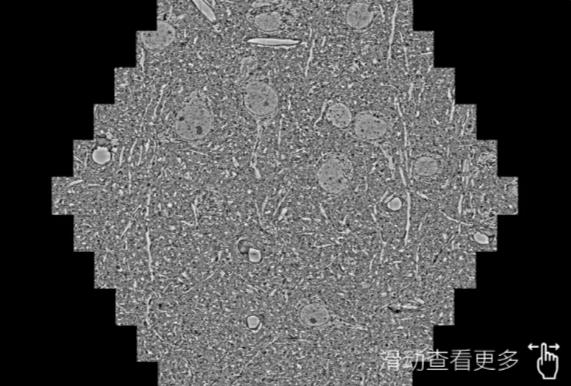

鼠脑切片。左图使用儋州蔡司儋州扫描电镜MultiSEM706对165μmx143pm面积区域成像,耗时仅需1.5秒。右图为鼠脑切片中30μm区域放大效果。样品由芝加哥大学B.Kasthuri提供。